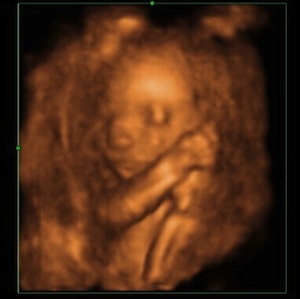

Noch mehr Bilder? Jetzt reichts erstmal. - Tagebücher aus der Schwangerschaft von Kristin aus Jena